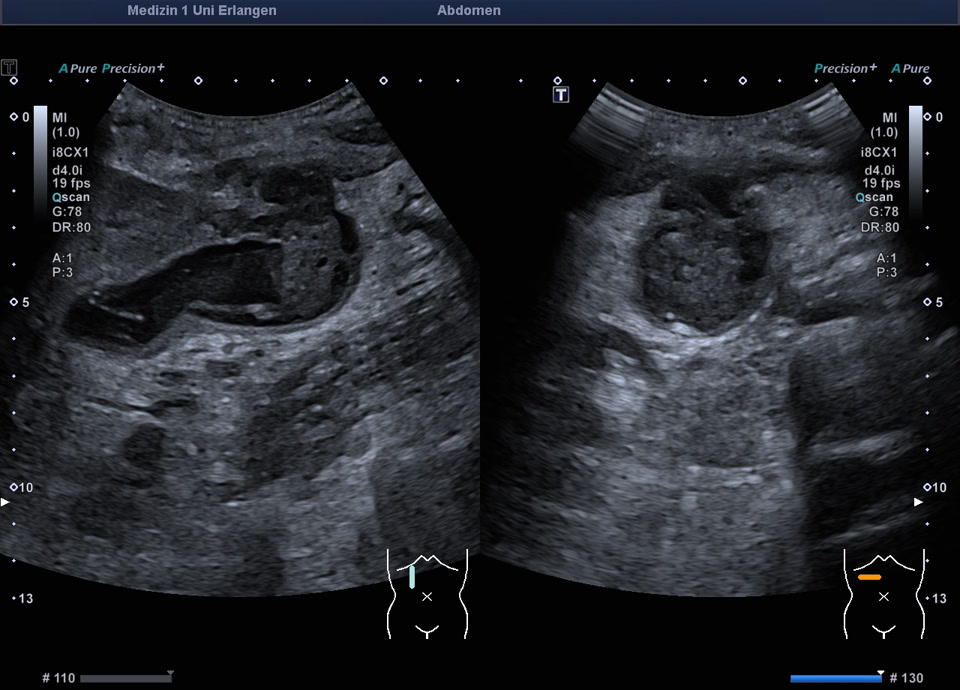

Perforierte Gallenblase (bei fortgeschrittenem Pankreaskarzinom mit Peritonealkarzinose), siehe auch folgendes Video

Perforierte Gallenblase (bei fortgeschrittenem Pankreaskarzinom mit Peritonealkarzinose)